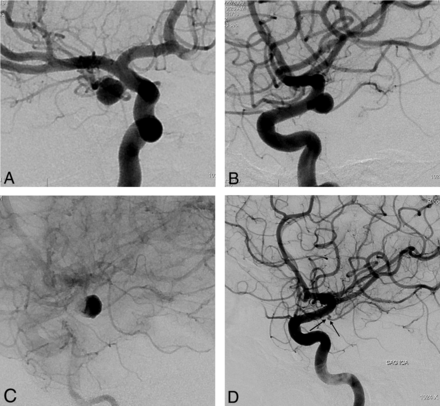

This retrospective study included 251 aneurysms treated with PEDs in 191 consecutive patients (mean age, 49.2 years; age range, 26–71 years; except for 1 pediatric patient who was 13 years of age) between November 2008 and September 2011. One hundred twenty-nine patients were female and 62 were male. Following ethics committee approval, 17 of the patients were included in the Pipeline for Uncoilable or Failed Aneurysms Study. Written informed consent was obtained from each patient. Sidewall aneurysms with wide necks (≥4 mm) or unfavorable dome-neck ratios (≤1.5) (Fig 1), large or giant aneurysms that might have or already had mass effect (Fig 2), fusiform aneurysms (Fig 3), blisterlike aneurysms (Fig 4), recurrent sidewall aneurysms, dissecting aneurysms (Fig 2), aneurysms at difficult angles to the parent artery (so that catheterization of the aneurysm and coiling may have increased risk) (Fig 5), and aneurysms in which a branch was originating directly from the sac (therefore endosaccular obliteration or clipping was likely to compromise the branch or result in a neck remnant) were treated with the PED (Figs 6 and 7). We intended to treat 1 patient with a giant, very wide-neck, cavernous ICA aneurysm presenting with mass effect symptoms by using a PED; however, we failed to bypass the neck of the aneurysm, resulting in treatment of the aneurysm with parent artery occlusion following a balloon occlusion test, without complications. This patient was not included in the study because a PED was not used. This was the only technical failure during the course of the series.

Lateral angiogram shows a giant dissecting ICA aneurysm (A). The intraoperative view demonstrates PEDs (sizes, 4 × 202 and 4.5 × 16 mm) opening to the normal size of the parent artery at the dissected segment (arrow in A) without necessitating balloon angioplasty. Note the contrast stagnation within the sac (B). Six-month control angiography (C) shows total occlusion of the aneurysm and reconstruction of the parent artery.

Left vertebral angiogram (A) demonstrates the left PCA aneurysm, which presented with left thalamic infarct (not shown). Immediate postoperative view (B) shows the single PED (2.5 × 20 mm) placed in the left PCA, resulting in contrast stasis within the sac. Control angiography (C) after 6 months confirms total occlusion of the aneurysm with the PCA preserved.

3D image (A) and lateral angiography (B) show a left paraophthalmic bleb aneurysm in a patient who had a subarachnoid hemorrhage 3 months earlier. Lateral angiogram 6 months after placement of a single PED of 3.75 × 12 mm (C) demonstrates complete occlusion of the aneurysm.

Right carotid angiogram (A) demonstrates a small carotid cave aneurysm in a patient who had an anterior communicating artery aneurysm previously treated with coiling following SAH. Six-month control angiography (B) shows occlusion of the aneurysm.

Preoperative 2D (A and B) angiograms show the ICA aneurysm in which the anterior choroidal artery is originating from the aneurysm at the neck. A single PED is placed covering the neck, causing stagnation of the contrast within the sac (C). Six-month control angiography (D) demonstrates total occlusion of the aneurysm with the anterior choroidal artery preserved (arrow).